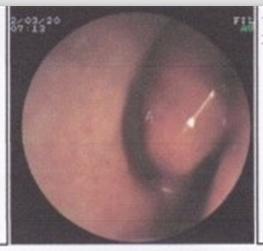

贵阳鼻甲肥大有何危害?鼻甲肥大是指鼻甲长期受到炎症的刺激引起鼻甲黏膜水肿,导致鼻腔阻塞。一般由慢性单纯性鼻炎发展而来、粘膜上皮纤毛脱落,变为复层立方上皮,粘膜下层由水肿继而发生纤维组织增生而使粘膜肥厚,久之,可呈桑椹状或息肉样变,骨膜及骨组织增生,鼻甲骨骨质也可呈肥大改变。